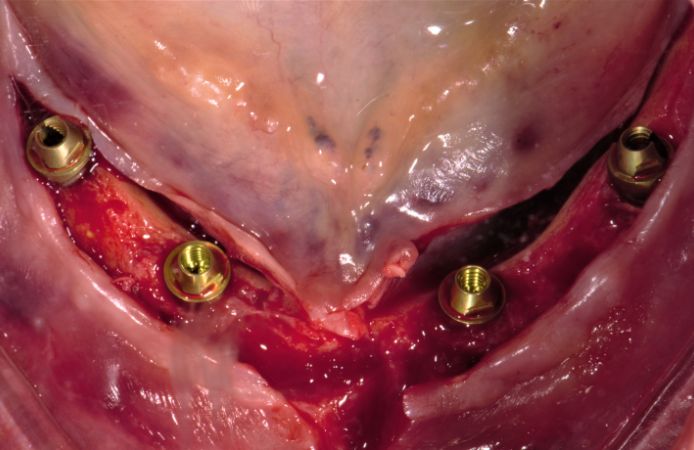

- Extraction of six teeth in the lower jaw.

- Immediate placement of four implants with Multi-Unit Abutments.

Figure 4.